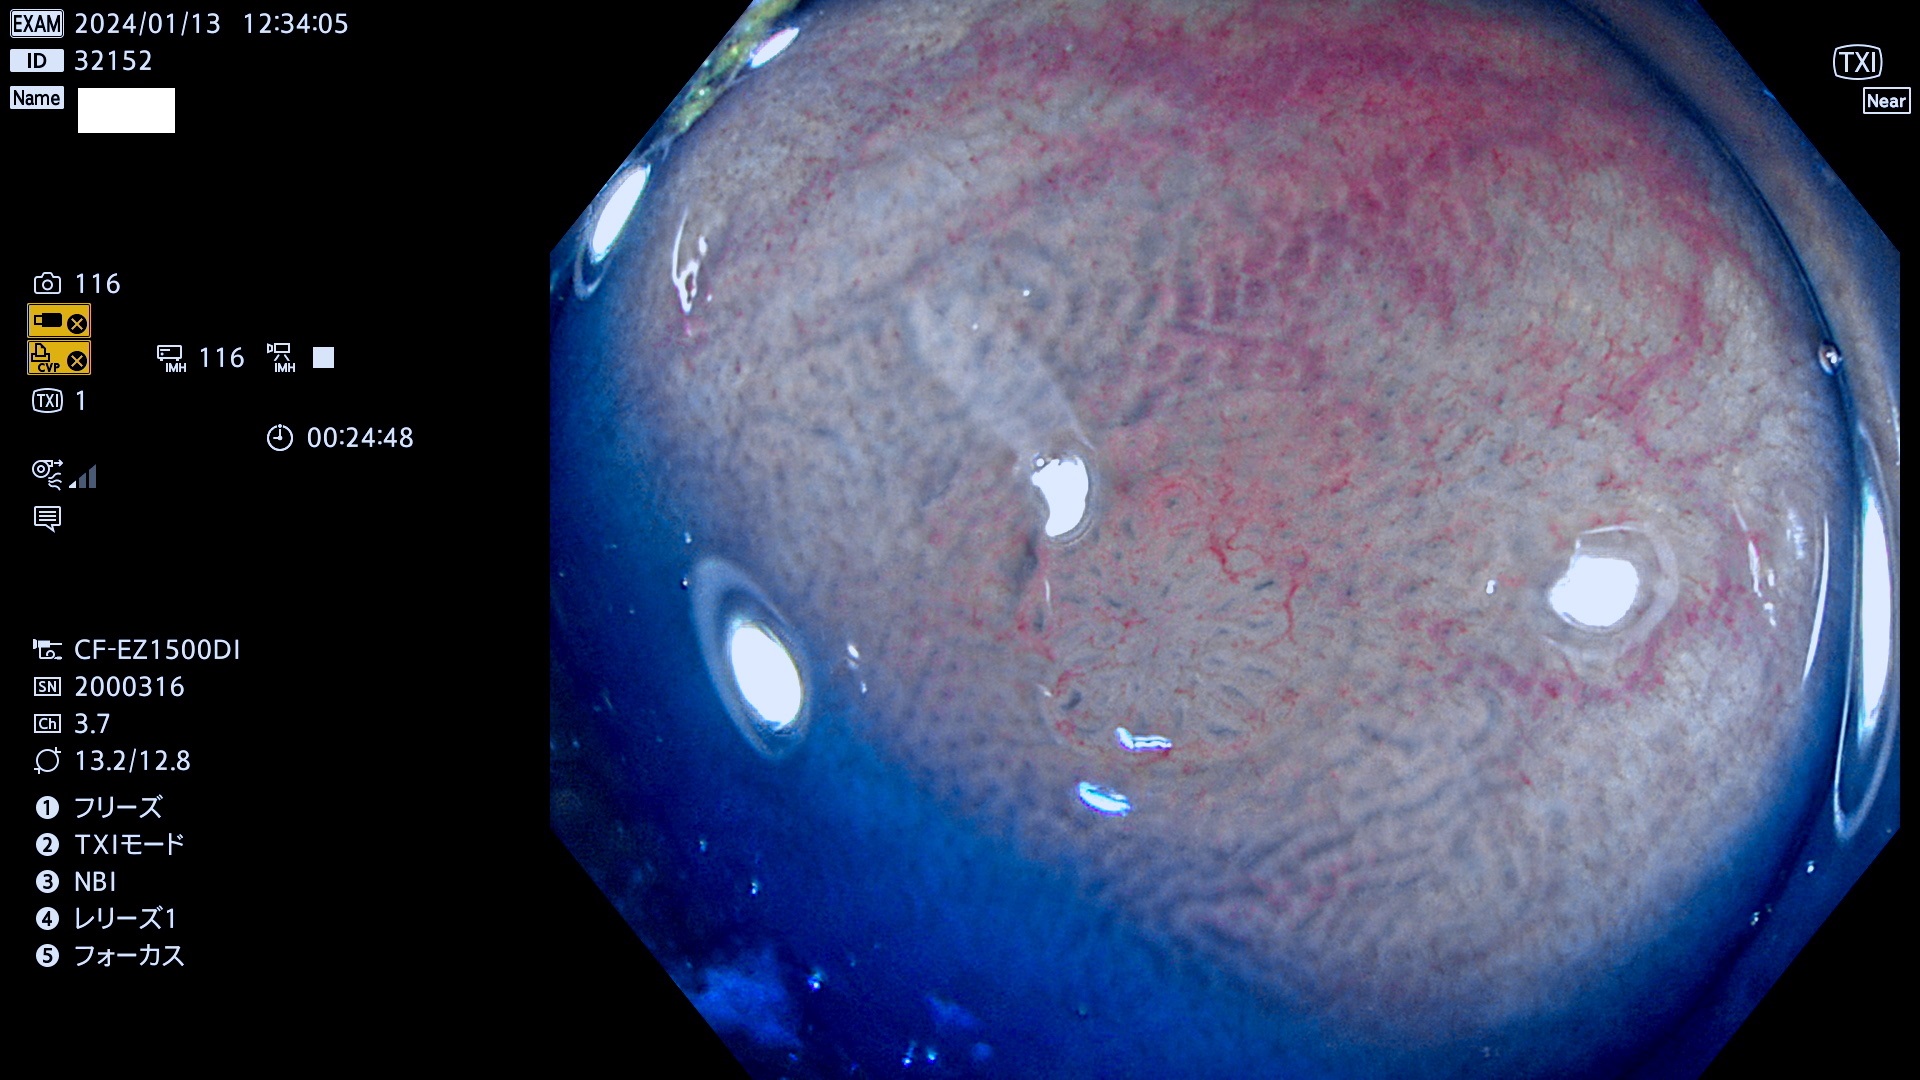

表面型腺腫(Flat Adenoma)の中で、完全に平坦な物をUb、陥凹している物をUcと呼びます。平坦隆起型(Ua)よりも、発見が難しく危険な病変です。

毎週の検査(木・金・土・日)に発見されたUb、Uc型・腺腫を、その週の日曜の夜にUPし1週間、提示します。

抽出の対象期間 2024年1月11日(木))〜1月14(日)の4日間(40件の検査)9件